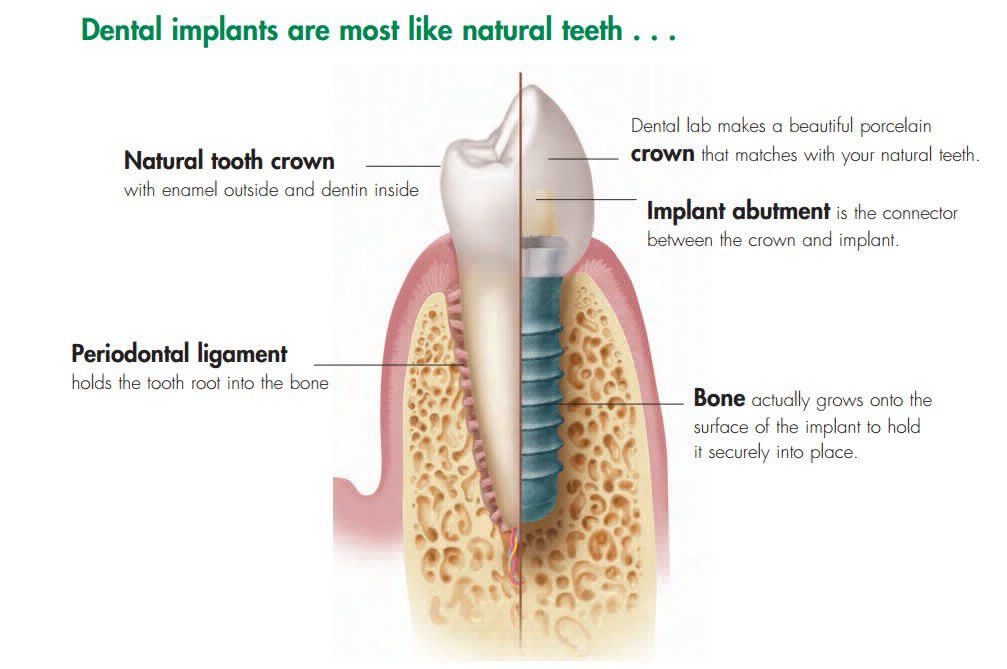

Dental Implant adalah solusi terbaik dari seluruh gigi tiruan. Pertama bentuk dan anatomy dari implant hapir sama dengan gigi asli. Warna dari mahkota gigi dapat disesuikan dengan gigi sebelahnya supaya terlihat gigi asli. Kedua dental implat merupakan gigi tiruan fixed yang tidapa dapat dilepas pasang, jadi aman tidak akan hilang. Ketiga tidak diperlukannya preparasi dari gigi sebelah kanan dan kiri sebagai penyangga. Dental implant menempel langsung di tulang yang kestabilannyua terjaga.